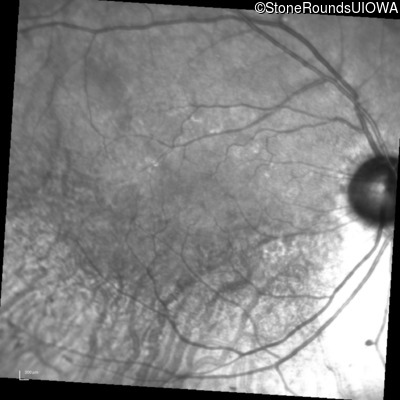

Infrared Fundus Photograph - Right - 20/20

Exemplar

Infrared Fundus Photograph - Left - 20/20